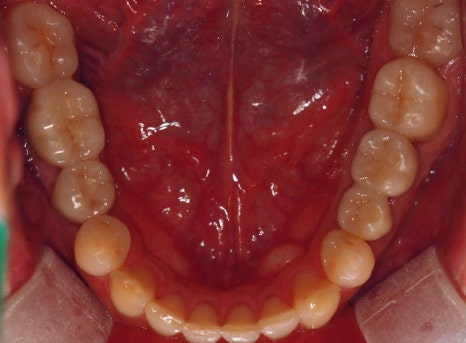

치료가 완료된 구강 사진을 보도록 하겠습니다.

▲치료 완료 후 파노라마 사진

이렇게 치료 최종 치료 기간까지는 23. 8월~24. 7월에 마무리하셔서 거의 1년 정도 소요가 되었습니다.